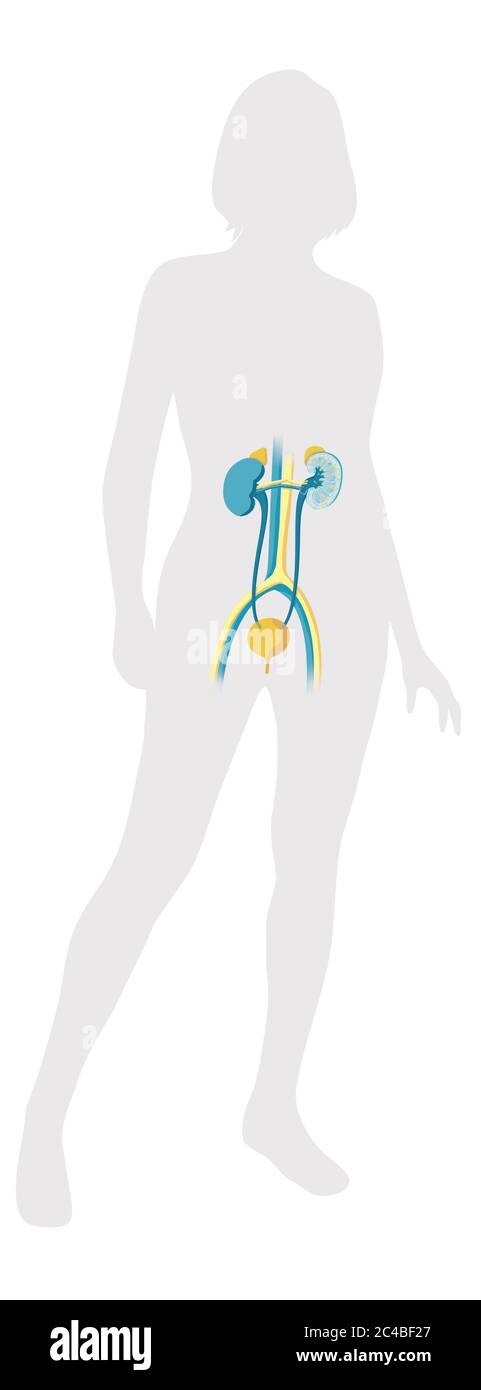

Voies urinaires féminines, vessie, reins, surrénales. Illustration médicale illustrant l'anatomie du système urinaire féminin dans une silhouette féminine. Ceci Banque D'Imageshttps://www.alamyimages.fr/image-license-details/?v=1https://www.alamyimages.fr/voies-urinaires-feminines-vessie-reins-surrenales-illustration-medicale-illustrant-l-anatomie-du-systeme-urinaire-feminin-dans-une-silhouette-feminine-ceci-image364129647.html

Voies urinaires féminines, vessie, reins, surrénales. Illustration médicale illustrant l'anatomie du système urinaire féminin dans une silhouette féminine. Ceci Banque D'Imageshttps://www.alamyimages.fr/image-license-details/?v=1https://www.alamyimages.fr/voies-urinaires-feminines-vessie-reins-surrenales-illustration-medicale-illustrant-l-anatomie-du-systeme-urinaire-feminin-dans-une-silhouette-feminine-ceci-image364129647.htmlRM2C4BF27–Voies urinaires féminines, vessie, reins, surrénales. Illustration médicale illustrant l'anatomie du système urinaire féminin dans une silhouette féminine. Ceci